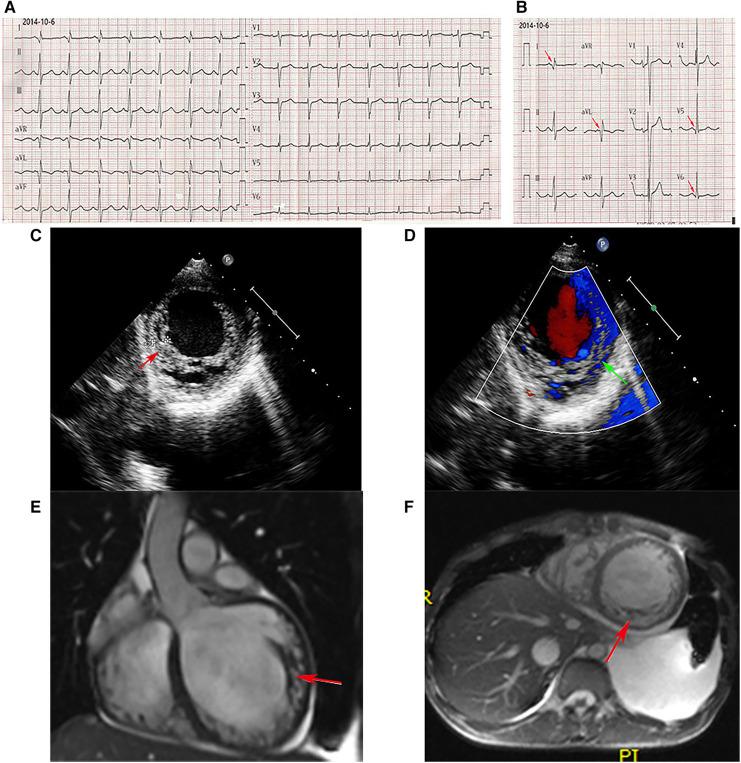

In the present study, we identified a deletion mutation in exons 10 to 12 (EX10_12 del) of the gene (reference sequence NM_004006.2) in two Chinese siblings with BMD and LVNC by high throughput targeted next-generation sequencing (NGS) and quantitative polymerase chain reaction (qPCR). The proband was a 22-year-old man admitted with dyspnea, abdominal distention, and polyserositis. It is noteworthy that both the proband and his younger brother manifested progressive muscular atrophy and creatine kinase (CK) elevation. Light and electron microscopy examination of muscle biopsies showed the typical features of dystrophinopathies. Cardiac magnetic resonance imaging and echocardiography demonstrated that both brothers had an enlarged left ventricle, LVNC, and reduced left ventricular ejection fraction. Finally, the proband underwent heart transplantation at age 26 with an event-free follow-up over 4 years post-transplantation.